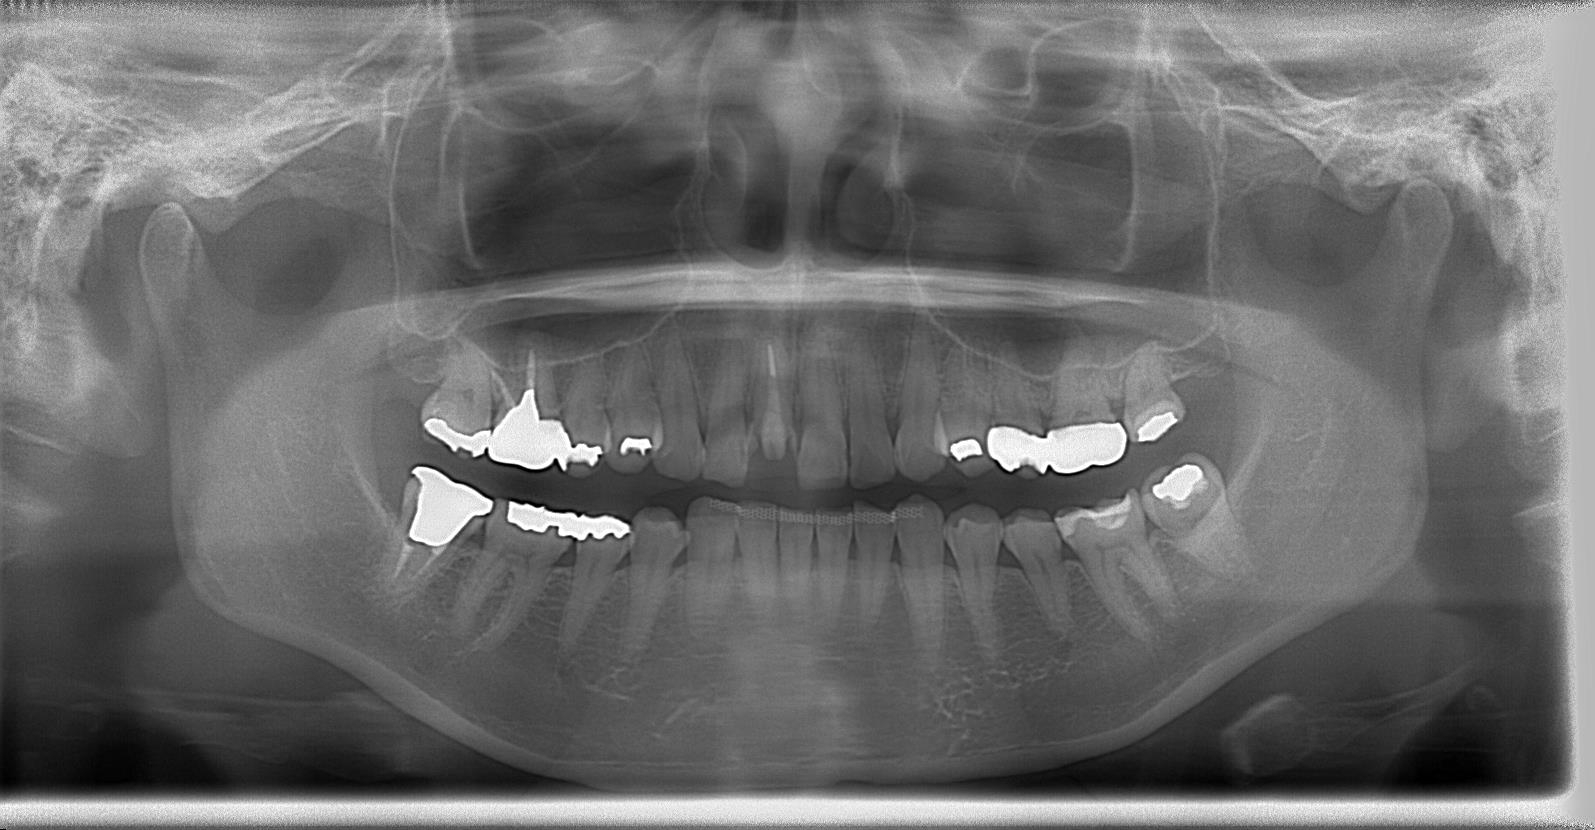

術前のパノラマレントゲン写真